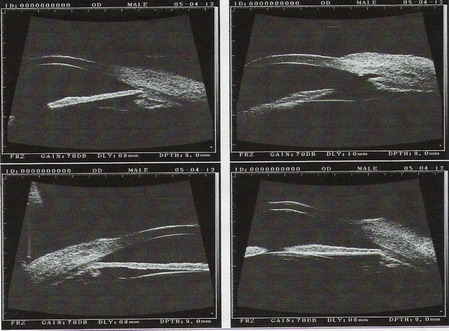

2005年4月12日右眼UBM图像

2003年9月16日B超:双眼玻璃体轻度混浊,右眼视网膜脱离

2003年11月12日B超:右眼玻璃体轻度混浊,右眼视网膜脱离

2004年3月2日B超:右眼视网膜脱离(鼻上)

2005年4月8日B超:右眼玻璃体轻度混浊,右眼视网膜脱离,视盘凹陷(青光眼型)